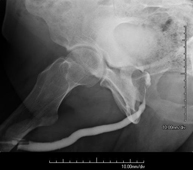

- Hipsterosalpingografía (HSG)

Prueba diagnóstica que consiste en la visualización y el estudio del útero y las trompas de Falopio mediante el empleo de rayos X y un medio de contraste. La paciente deberá realizar un tratamiento antibiótico profiláctico. Se recomienda la toma de un sedante suave una hora antes de la prueba.